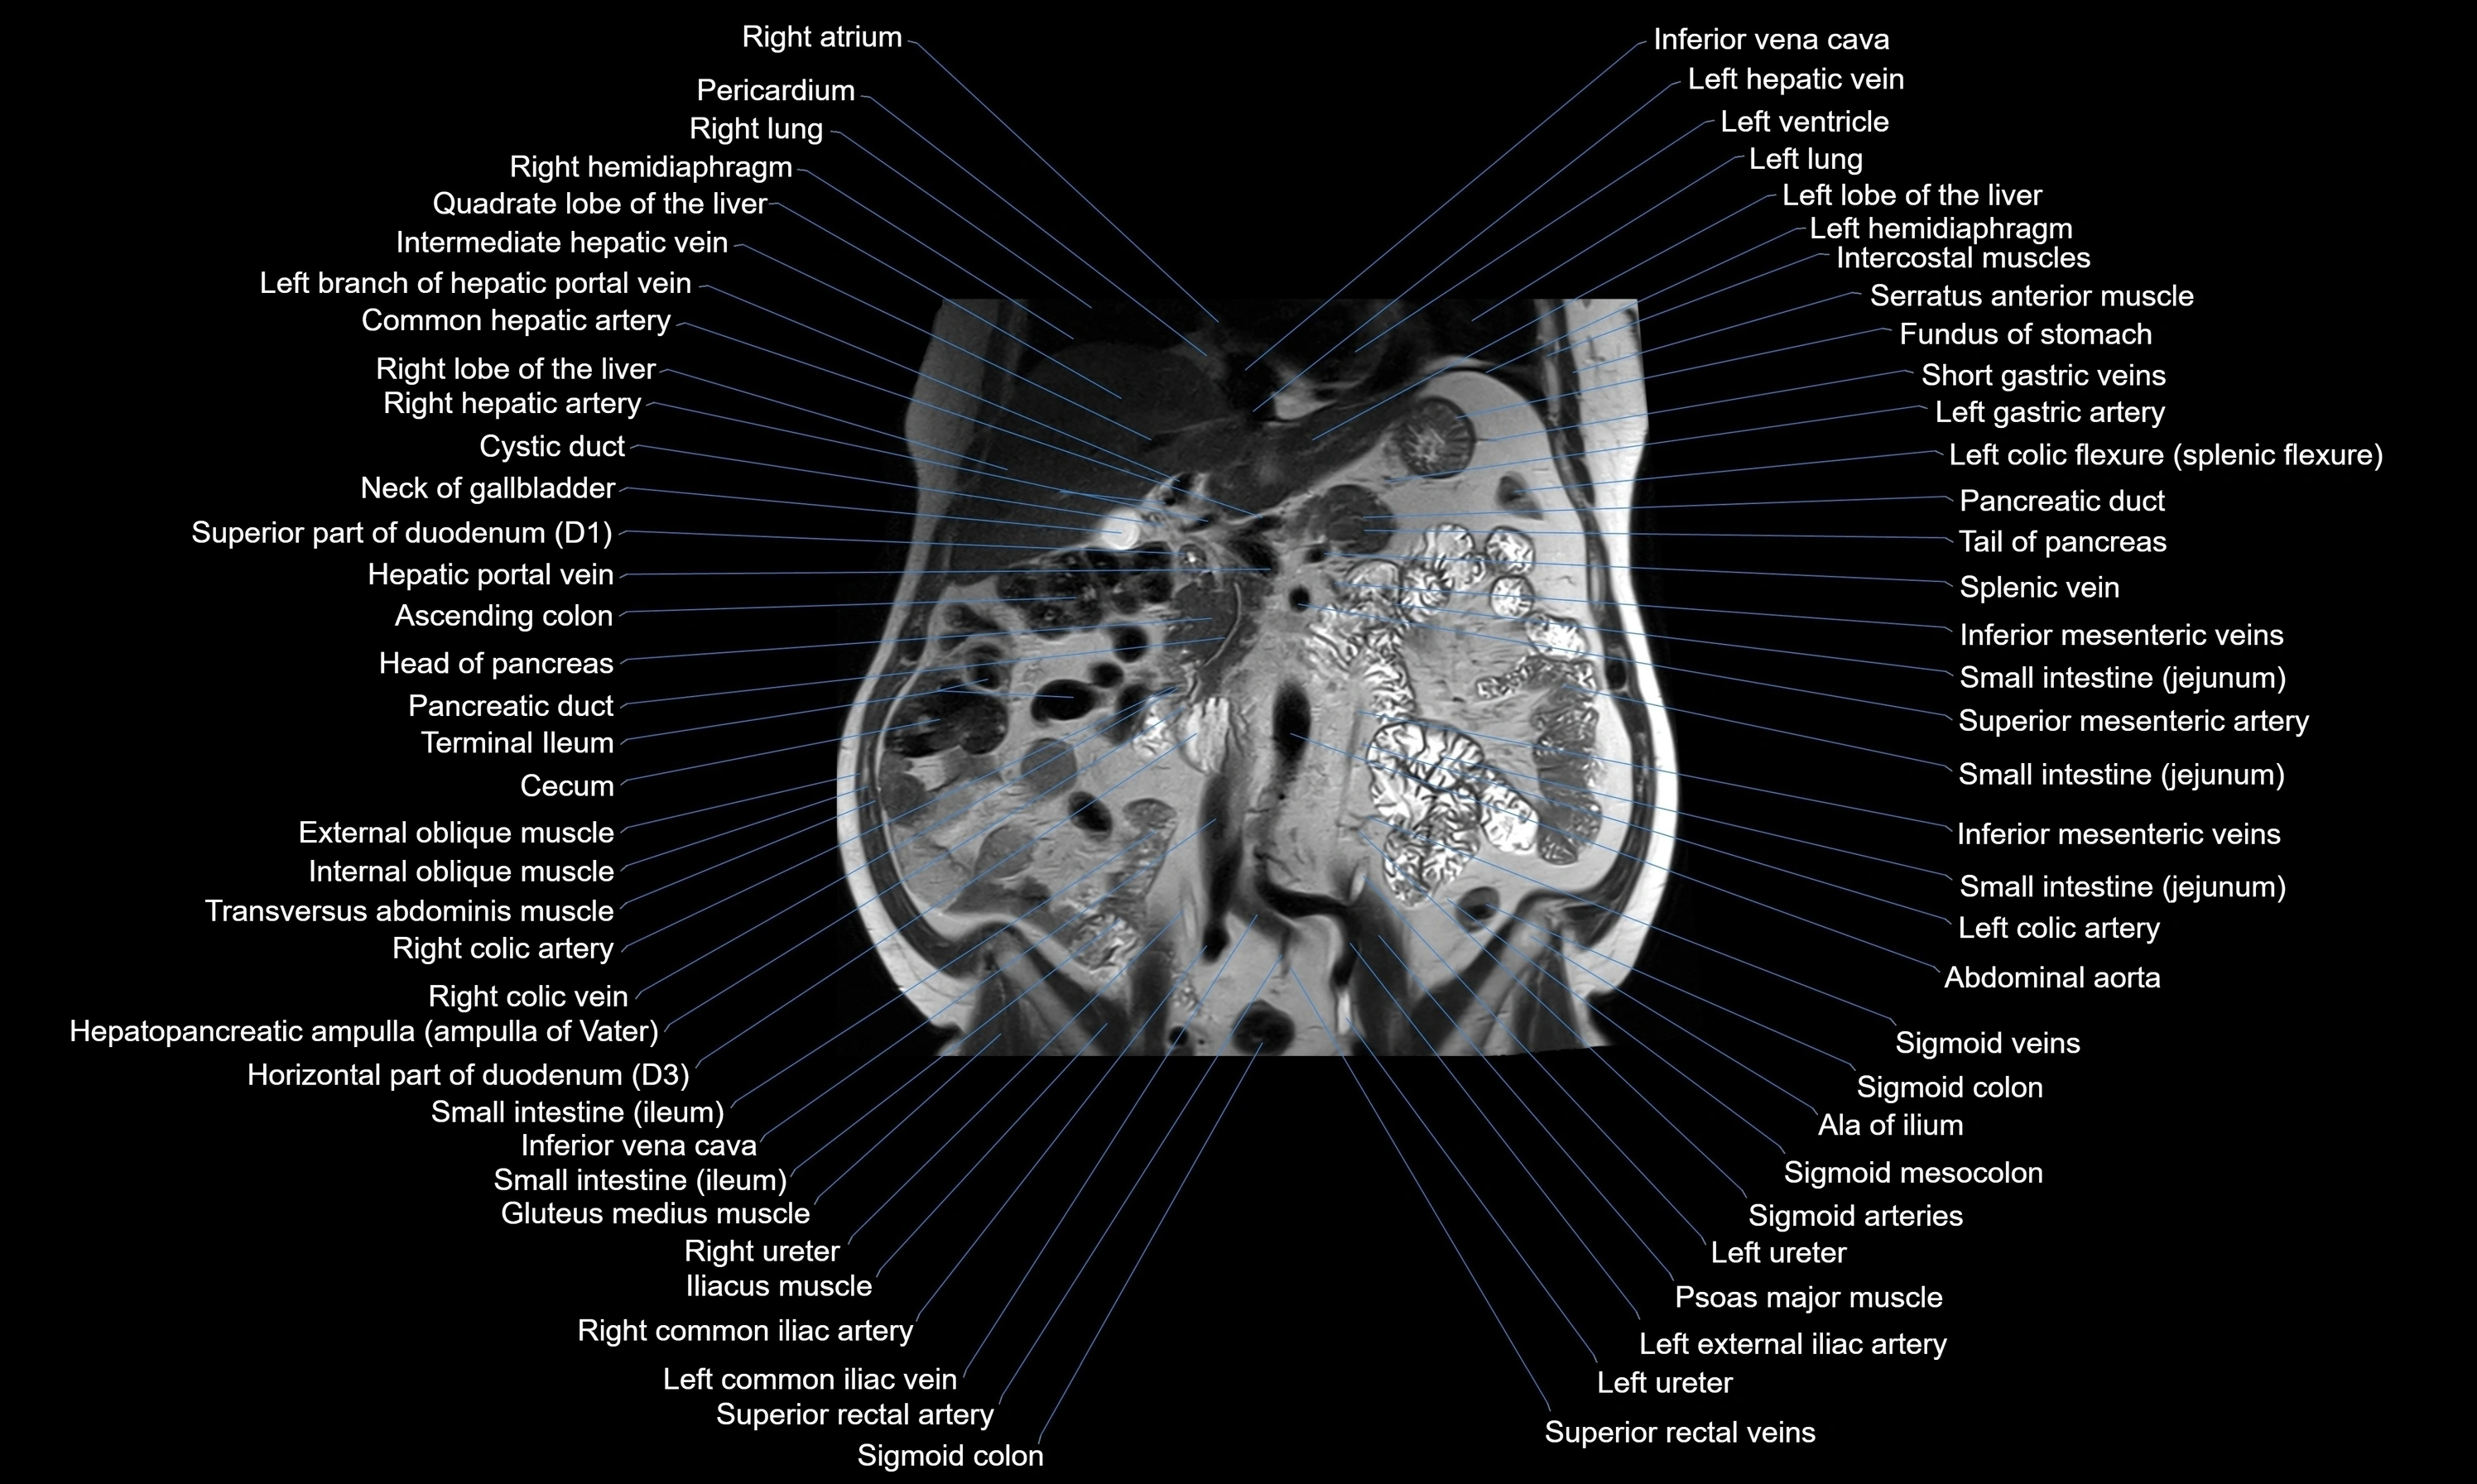

MRI images